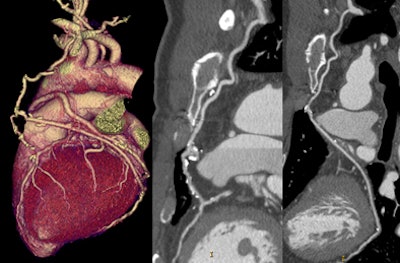

Patient doses ranged from 0.75 to 6.67 mSv (mean 2.84 mSv ± 1.3 mSv), representing a mean 83.2% reduction compared to the RGH control group (8.7 to 23.2 mSv, mean 18.4 mSv, p < 0.001).

![]() |

| Use of the PGA technique reduced the mean radiation dose by more than 83% compared to standard retrospectively gated coronary CT angiography on the same 64-slice scanner. |

The mean Hounsfield unit density was slightly higher with PGA compared to RGH for the left main, left anterior descending, left circumflex, and right coronary arteries, as well as the aortic root and midleft ventricle. Image noise was consistently lower for the RGH patients, owing to the addition of a noise filter for this group, and the signal-to-noise ratio was consistently higher (p < 0.01).

Image quality was high for both groups, and slightly higher for the PGA patients (mean 4.79 versus 4.51 for the RGH group) across all coronary arteries, a statistically significant difference (p < 0.001; the 95% confidence interval on the image quality increase was 0.20-0.36). Based on image quality scores (two or less considered unevaluable), 1.39% of PGA scores versus 2.11% of RGA scores were deemed nonevaluable. Most patients receiving doses less than 1 mSv were quite thin -- all had BMI scores of 21 or lower.